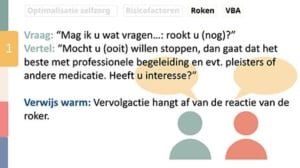

De omnicalculator biedt allerlei reken tools zo is een handige tool om onder andere het packyear van een patiënt uit te rekenen om te praten met de patiënt over roken en de risico’s daarvan. Veelal zijn de rekentools ondersteunt met wetenschappelijke literatuur. Roken kan namelijk zorgen voor peri-implantitis, meer implantaat verlies, verlies van gebitselementen, invloed om de gebitstoestand van kinderen en verlies van elementen in de nazorg. Stoppen met roken kan juist zorgen voor aanhechtingswinst, pocketdiepte reductie, minder risico op parodontitis en lagere incidentie of progressie.

Klik hier voor een vergrote afbeelding

In de praktijk is het noodzakelijk om het rookgedrag te bespreken. Waar voorheen motivational interviewing de standaard is dat tegenwoordig volgens het Trimbos het zogenoemnde VBA (very brief advice). Hierbij gaat het om het stellen van de vraag of er nog gerookt wordt, informeren naar de interesse om te stoppen, als die er is er de mogelijkheid om warm te verwijzen naar professionals die daar op gericht zijn.